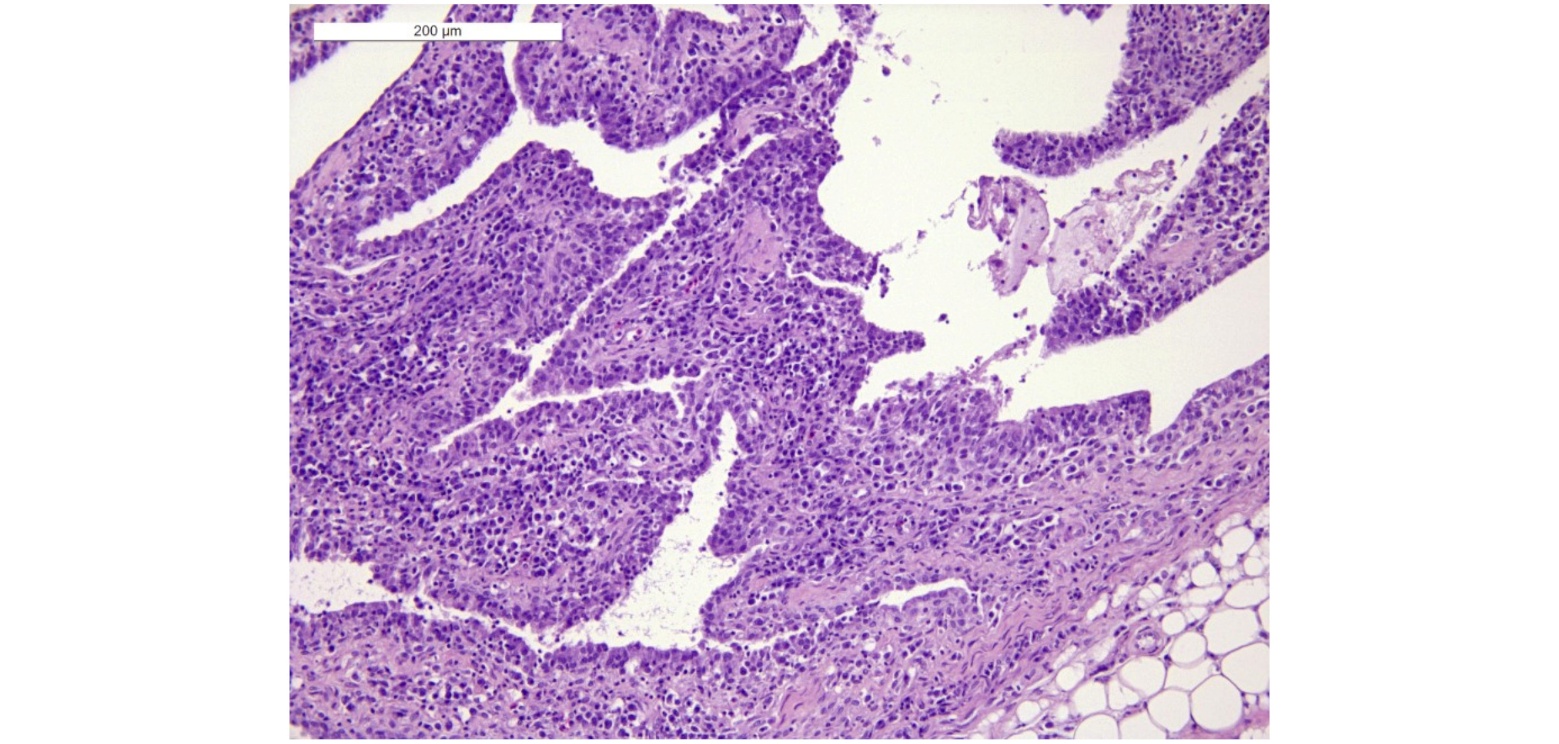

The synoviocytes were hyperplastic with lymphoplasmacytic infiltrate and scant fibrinoheterophilic exudate in the synovial space (Figure 9).

Figure. 9. Diffuse hyperplasia of the synoviocytes with lymphoplasmacytic infiltrate. Haematox-ylin and Eosin (H E) staining. 20X.